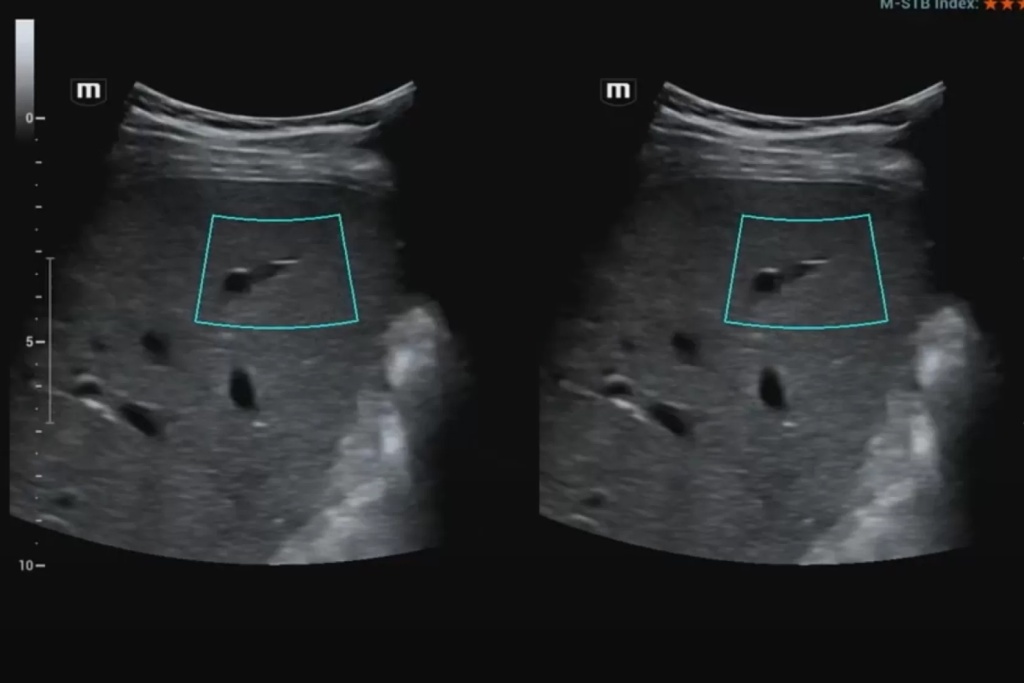

Эластография сдвиговой волной позволяет получить абсолютные значения жесткости исследуемой ткани. В основе данного метода лежит оценка скорости распространения поперечной (боковой) волны, которая может вызываться кратковременным механическим воздействием определенной силы и продолжительности на поверхность тела пациента (это так называемая транзиентная эластография) или сфокусированным усиленным акустическим импульсов в толще исследуемой ткани (именно данные методики в литературе обозначаются как эластография сдвиговой волной). Они в свою очередь подразделяются на методики точечной и двумерной эластографии.